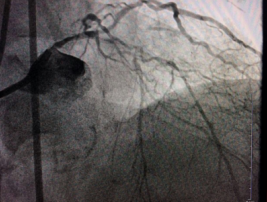

三支血管嚴重鈣化病變 ??患者主動要求實行微創(chuàng)介入治療

????入院后,經(jīng)冠脈造影術(shù)檢查顯示,陳大爺?shù)淖笾鞲杉叭Т笱埽ㄇ敖抵?、回旋支、右冠狀動脈)都發(fā)生了彌漫性病變,尤其是左冠狀動脈前降支、回旋支伴隨著嚴重的鈣化病變,最狹窄處堵塞達到95%;右冠狀動脈也存在嚴重鈣化病變,鈣化物幾乎將整個血管堵滿,導致心肌缺血出現(xiàn)胸悶胸痛癥狀。

術(shù)前

術(shù)前,介入專家首先對陳大爺進行了冠脈血管內(nèi)超聲檢查,明確血管內(nèi)結(jié)構(gòu)以及鈣化病變位置和嚴重程度。然后將帶有鉆石顆粒的高速旋磨頭送入患者血管內(nèi)的鈣化部位,在醫(yī)生的精細操作下,位于血管內(nèi)的磨頭便以每分鐘10多萬次的轉(zhuǎn)速開始高速旋轉(zhuǎn),根據(jù)“差異性切割”(即只針對嚴重鈣化和纖維化的病變斑塊組織而不損傷正常組織)原理,將阻塞血管的動脈斑塊迅速磨成極其微小的顆粒,隨血液循環(huán)至血管遠端并通過毛細血管床吸收。經(jīng)過幾次旋磨后,阻塞血管腔的鈣化斑塊被逐漸消除,在進行球囊擴張之后,在兩支血管內(nèi)順利植入四枚支架,成功開通血管,手術(shù)時間總共用時1個多小時。

術(shù)后